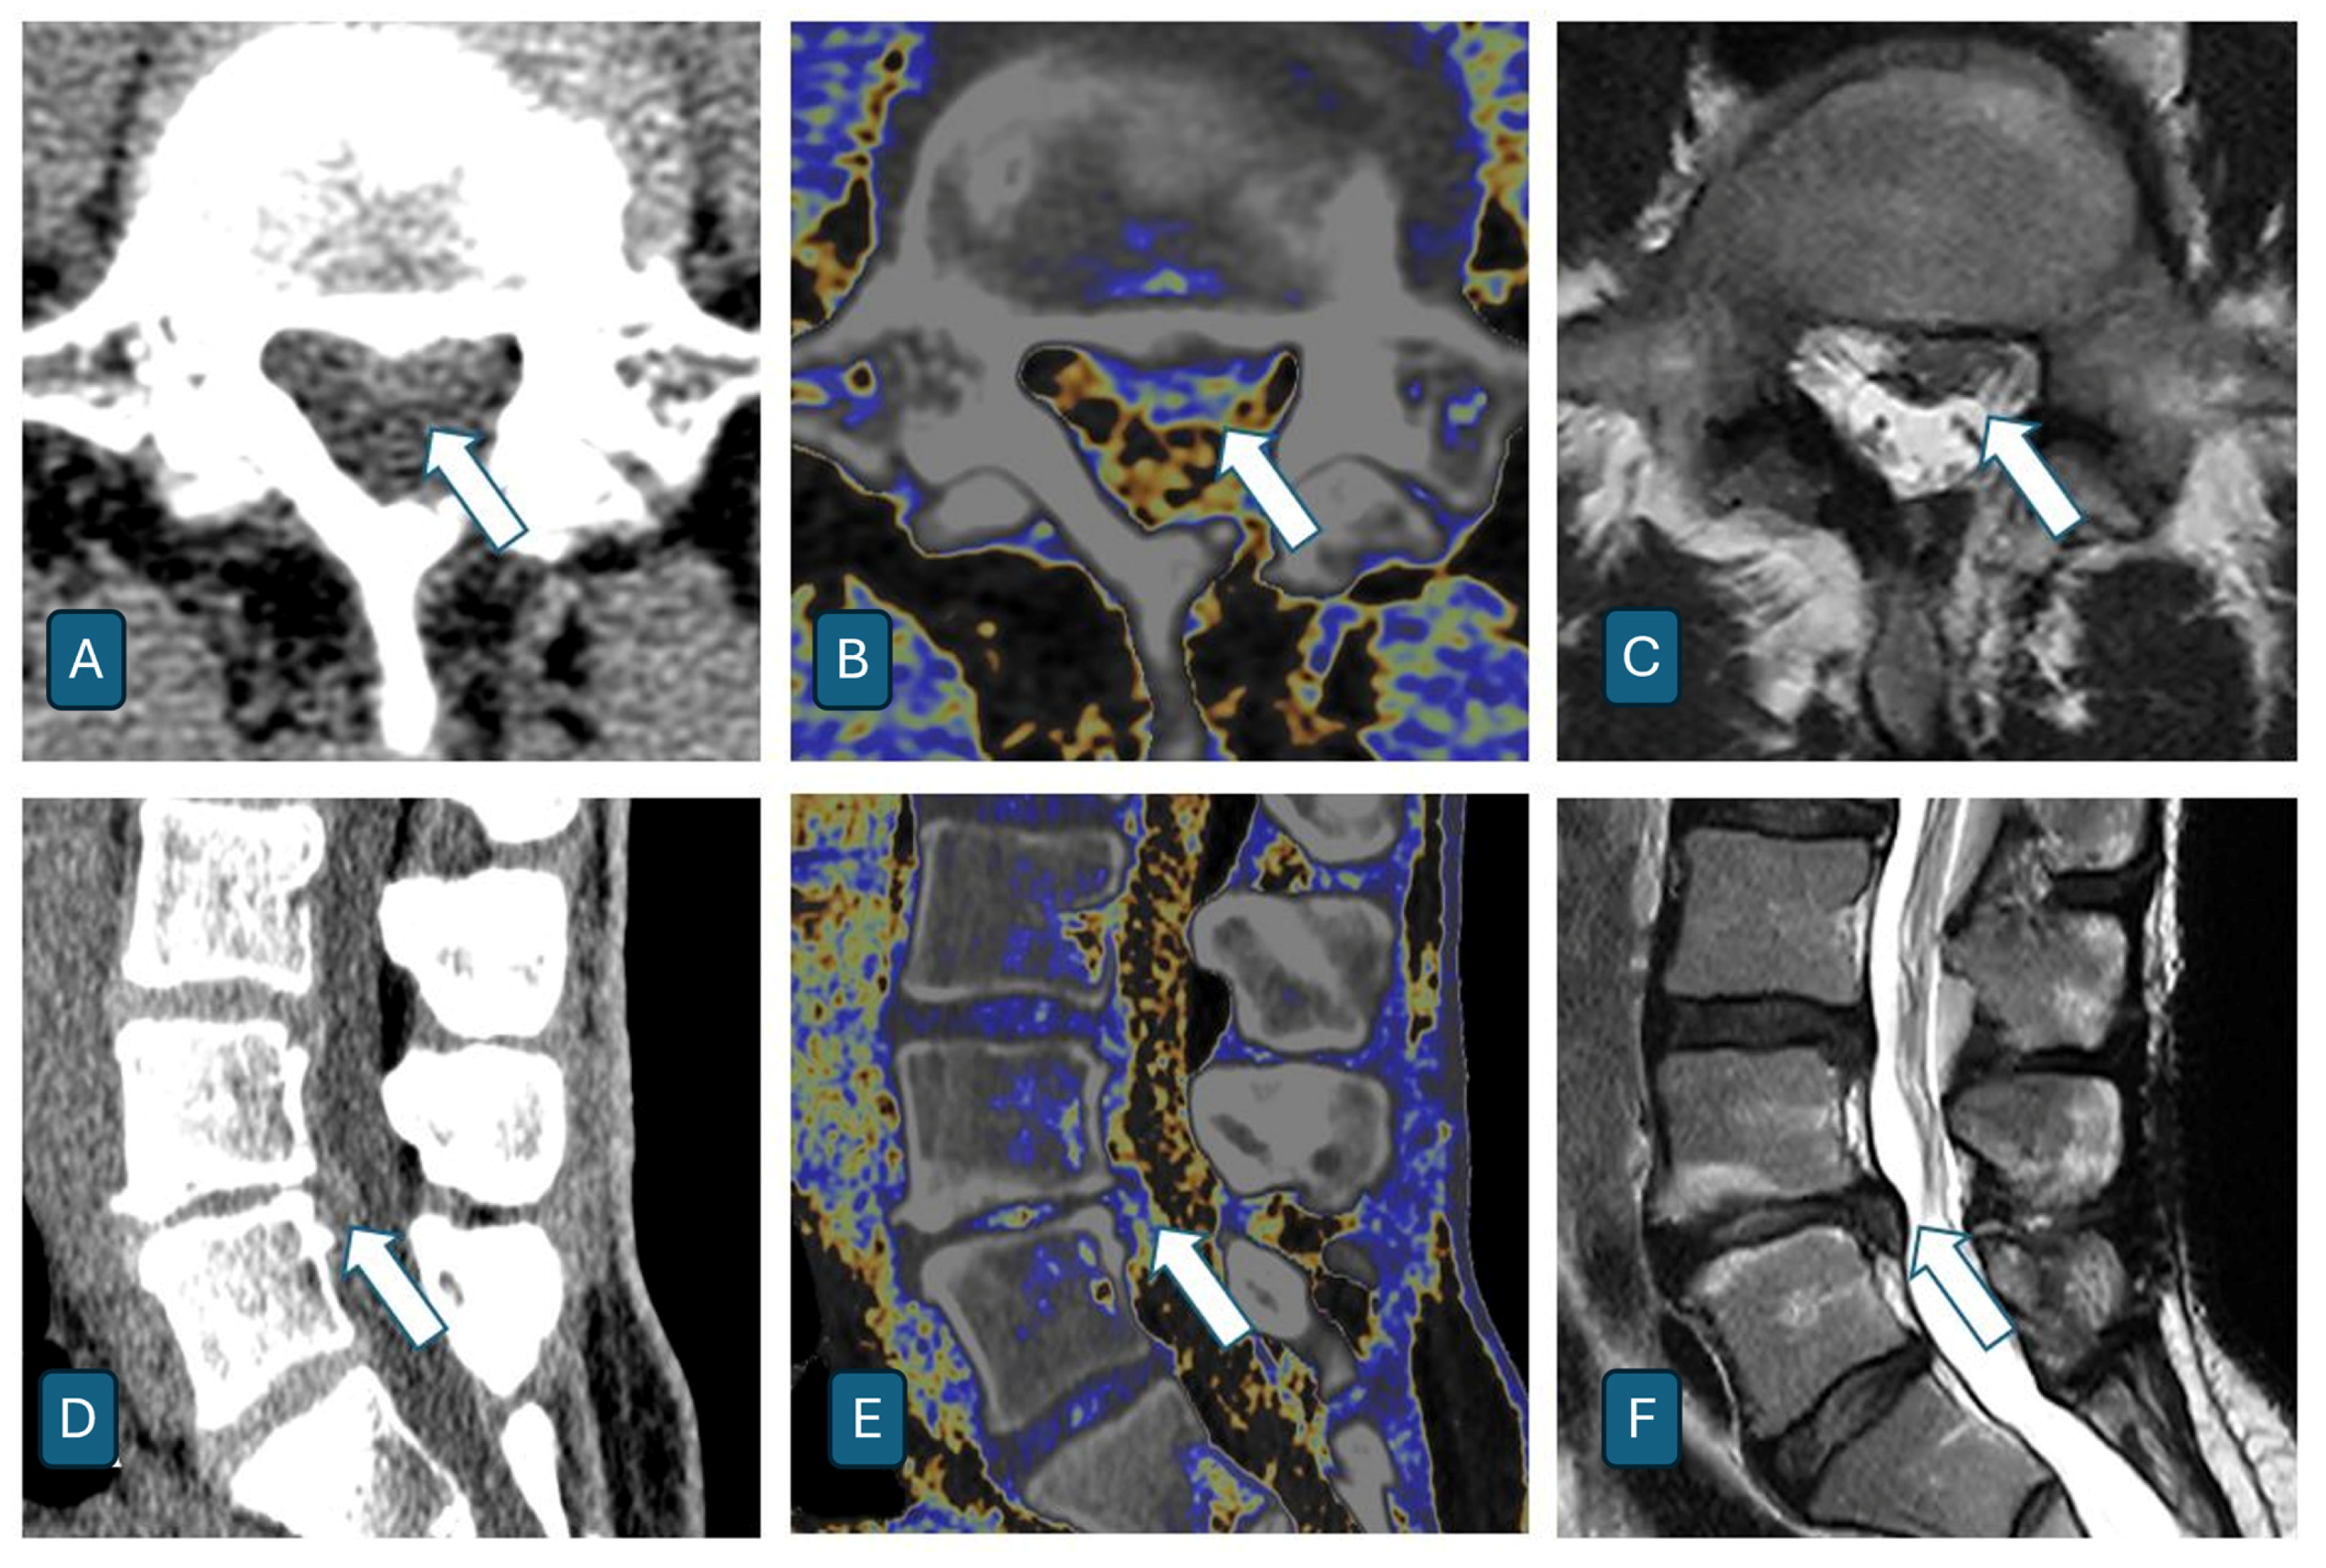

- Shim, E.; Kim, B.H.; Kang, W.Y.; Hong, S.J.; Kang, C.H.; Ahn, K.S.; Lee, H.; Kwack, T.J. Diagnostic performance of electron-density dual-energy CT in detection of cervical disc herniation in comparison with standard gray-scale CT and virtual non-calcium images. Eur. Radiol. 2022, 32, 2209–2220. [Google Scholar] [CrossRef] [PubMed] [PubMed Central]

- Booz, C.; Nöske, J.; Martin, S.S.; Albrecht, M.H.; Yel, I.; Lenga, L.; Gruber-Rouh, T.; Eichler, K.; D’Angelo, T.; Vogl, T.J.; et al. Virtual Noncalcium Dual-Energy CT: Detection of Lumbar Disk Herniation in Comparison with Standard Gray-scale CT. Radiology 2019, 290, 446–455. [Google Scholar] [CrossRef] [PubMed]